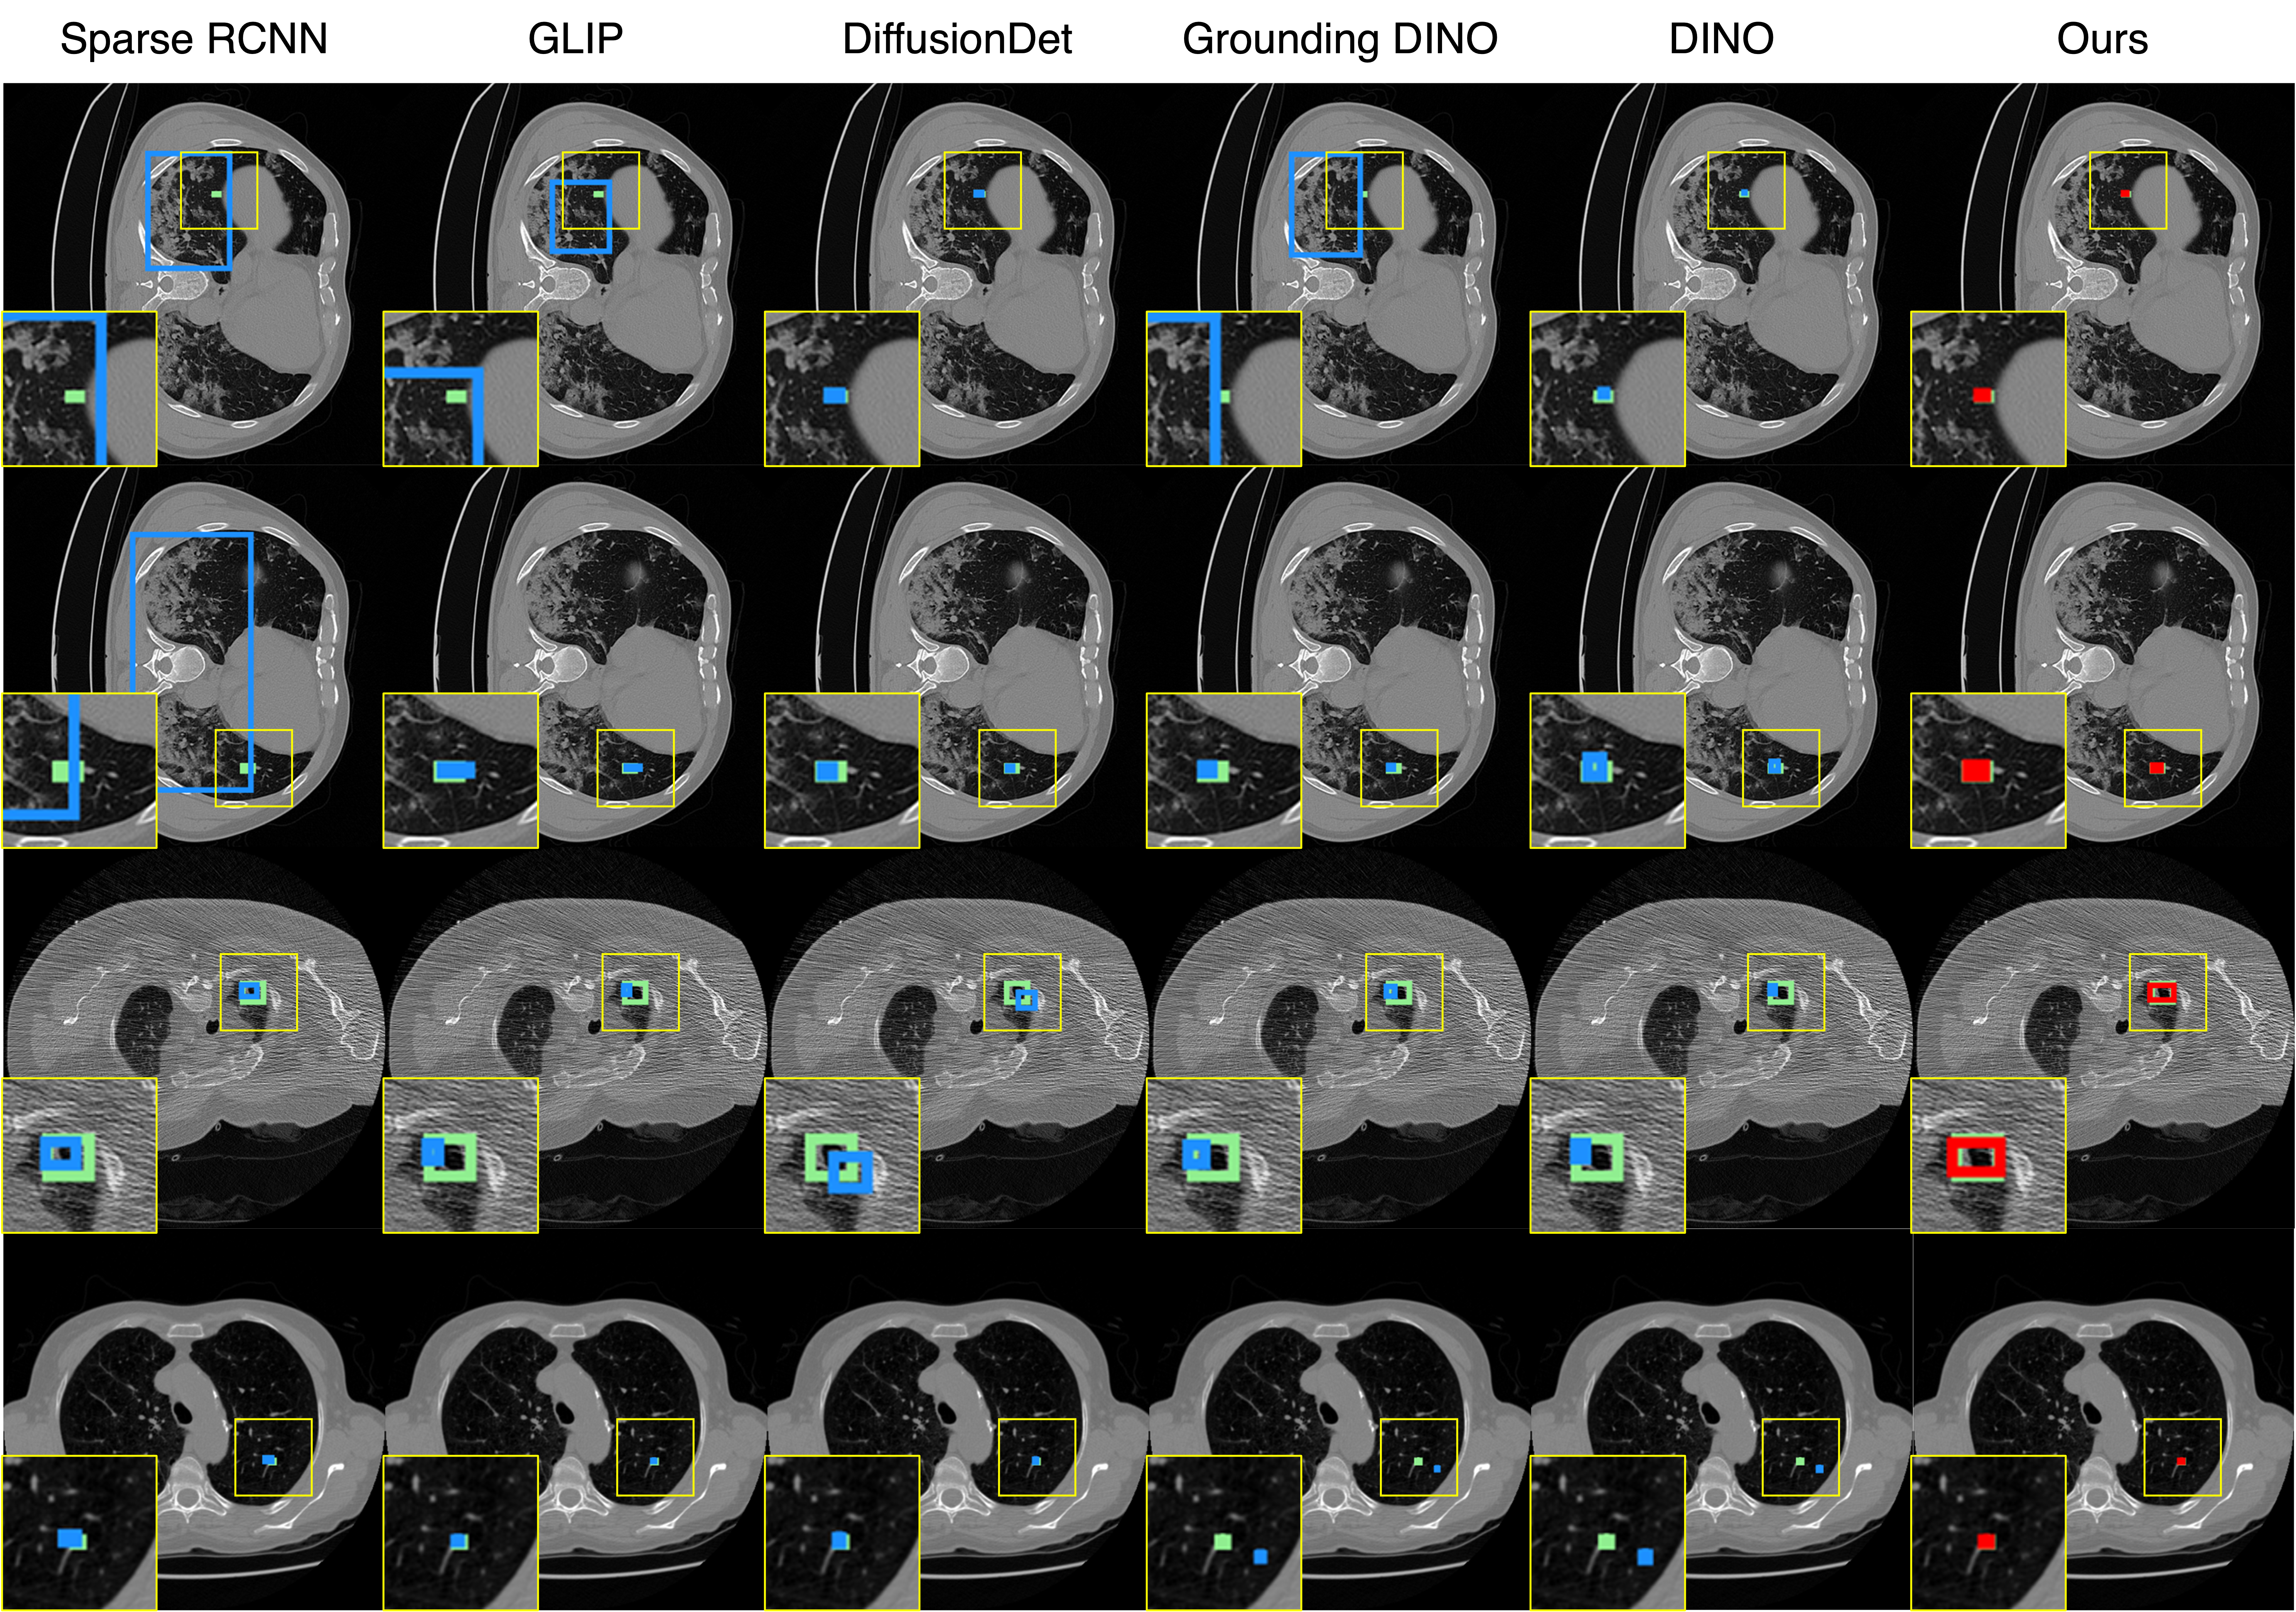

Qualitative comparison results

Qualitative Comparison. Comparison results between various state-of-the-art detection methods and the proposed method is shown above. Our method effectively leverages modality context to significantly enhance anomaly localization (red), compared to baseline results (blue). Ground truth bounding boxes are green. For cases where the bounding boxes are small, insets show an enlarged view of the highlighted yellow region.